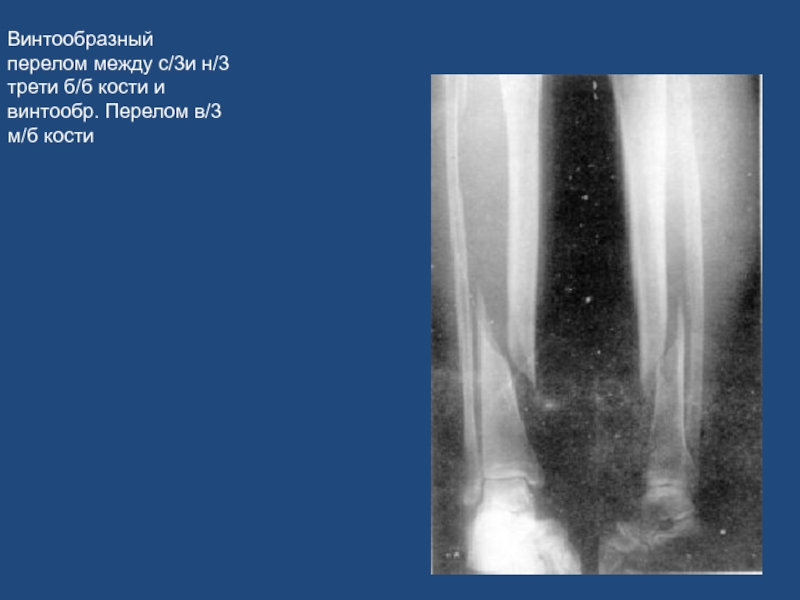

Слайд 67Винтообразный перелом между с/3и н/3 трети б/б кости и винтообр.

Перелом в/3 м/б кости

Винтообразный перелом между с/3и н/3 трети б/б кости и винтообр. Перелом в/3 м/б кости